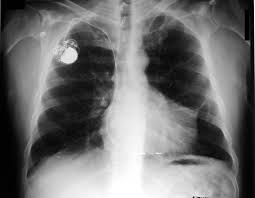

In radiology, a solitary pulmonary nodule (SPN) or coin lesion is a mass in the lungsmaller than 3 centimeters in diameter. It can be an incidental finding found in up to 0.2% of chest X-rays and around 1% of CT scans. The nodule most commonly represents a benign tumor such as a granuloma orhamartoma, but in around 20% of cases it represents a malignant cancer, especially inolder adults and smokers. Conversely, 10 to 20% of patients with lung cancer are diagnosed in this way. Thus, the possibility of cancer needs to be excluded through further radiological studies and interventions, possibly including surgical resection. Theprognosis depends on the underlying condition. A solitary pulmonary nodulus needs to be separated from larger lung tumors, smaller infiltrates or masses with other accompanying characteristics. An often used formal radiological definition is the following: a single lesion in the lung completely surrounded by lung parenchyma (functional tissue) with a diameter less than 3 cm and without associatedpneumonia, atelectasis (lung collapse) or lymphadenopathies (swollen lymph nodes). ot every round spot on a radiological image is a coin lesion: it should not be confused with the projection of a structure of the chest wall or skin, such as a nipple, a healing rib fracture or electrocardiographic monitoring.

The most important cause to exclude is a form of lung cancer, including rare forms such as primary pulmonary lymphoma, carcinoid tumor and a solitary metastasis to the lung (common unrecognised primary tumor sites are melanomas, sarcomas or testicular cancer). Benign tumors in the lung include hamartomas and chondromas. The most common benign coin lesion is a granuloma (inflammatory nodule), for example due to tuberculosis or a fungal infection. Other infectious causes include a pulmonary abscess, pneumonia (including Pneumocystis carinii pneumonia) or rarely nocardial infection or worm infection (such as dirofilariasis or dog heartworm infestation). Lung nodules can also occur in immune disorders, such asrheumatoid arthritis or Wegener's granulomatosis, or organizing pneumonia.

An SPN can be found to be an arteriovenous malformation, a hematoma or an infarction zone. It may also be caused by bronchial atresia, sequestration, an inhaled foreign body or pleural plaque. Several features help to distinguish benign conditions from possible lung cancer. The first parameter is the size of the lesion: the smaller, the less risk for malignant cancer. Benign causes tend to have a well defined border, whereas lobulated lesions or those with an irregular margin extending into the neighbouring tissue tend to be malignant.  If there is a central cavity, then a thin wall points to a benign cause whereas a thick wall is associated with malignancy (especially 4mm or less versus 16mm or more). In lung cancer, cavitation can represent central tumor necrosis (tissue death) or secondary abscessformation. If the walls of an airway are visible (air onchogram), bronchioloalveolar carcinomais a possibility. An SPN often contains calcifications. Certain patterns of calcification are reassuring, such as the popcorn-like appearance of hamartoma. An SPN with a density below 15 Hounsfield units on computed tomography tends to be benign, whereas malignant tumors often measure more than 20 Hounsfield units. Fatty tissue inside hamartomas will have a strongly negative value on the Hounsfield scale. The growth velocity of a lesion is also informative: very fast or very slow growing tumors are rarely malignant, in contrary to inflammatory or congenital conditions. It is therefore important to retrieve previous imaging studies to see if a lesion was presented and how fast its volume is increasing. This is more difficult for nodules smaller than 1 centimeter. Moreover, the predictive value of stable lesion over a period of 2 years has been found to be rather low and unreliable. The work-up in patients with a solitary pulmonary nodule is based on an initial risk assessment. If the risk of malignancy is thought to be low, follow-up imaging (usually serial CT scans) can be planned at a later time. The frequency of further scans can be determined by the patient's risk for cancer and the size of the nodule. If the initial impression is that there is a high likelihood of cancer, then a surgical intervention is appropriate (provided that the patient is fit for surgery). If there is an intermediate risk of malignancy, further imaging with positron emission tomography (PET scan) is appropriate (if available). Around 95% of patients with a malignant nodule will have an abnormal PET scan, while around 78% of patients with a benign nodule will look normal on PET (this is the test sensitivity and specificity). Thus, an abnormal PET scan will reliably pick up cancer, but several other types of nodules (inflammatory or infectious, for example) will also show up on a PET scan. If the nodule has a diameter below 1 centimeter, PET scans are often avoided because there is an increased risk of falsely normal results. Cancerous lesions usually have a high metabolism on PET, as demonstrated by their high uptake of FDG (a radioactive sugar). If the lesion is found on further imaging to be suspicious, it should be surgically excised (via thoracotomy or video-assisted thoracic surgery) to confirm the diagnosis by microscopical examination.